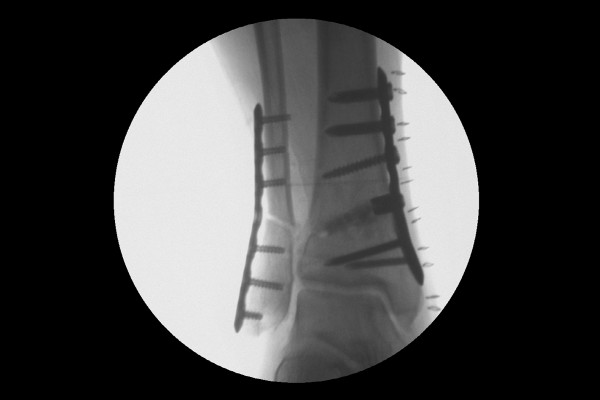

바깥쪽 뼈도 마찬가지로 실금을 내어 금속판으로 고정하여, 체중부하를 내측에서 외측으로 이동시킵니다.

수술 후 X-RAY에서 잘 고정되었고, 발목 안쪽의 공간이 생긴 것이 확인됩니다.

수술 전/후 X-RAY를 비교해보면 더욱 확실하게 알 수 있습니다.